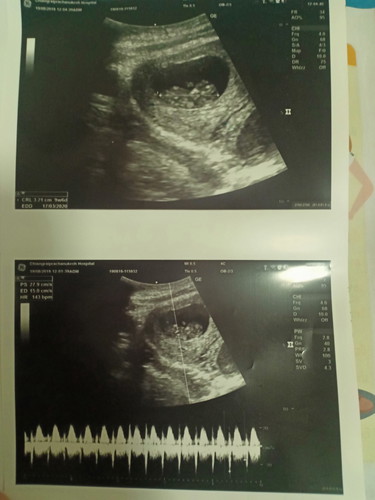

นับตามปฏิทิน12w3d ใบซาววันนี้9w6d. เจอน้องแล้วค่ะพร้อมกับหัวใจดวงน้อยๆเต้นตุบๆ?รู้สึกมีความสุขอย่างบอกไม่ถูกในที่สุดก่อเจอหลังจากที่ลุ้นกันมา